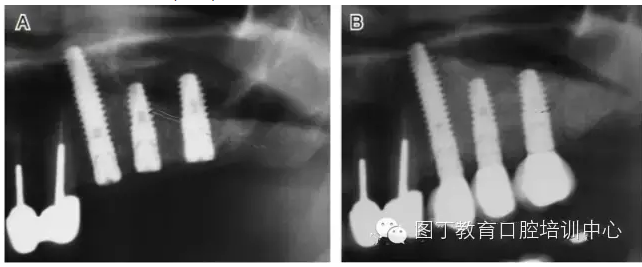

臨床上,可使用曲面體層放射線法及CT掃描方法對上額竇及可用骨量進行評估。其中曲面體層放射線法可提供多數(shù)病例的硬腭致密影像,為治療計劃提供有價值的參考(圖1);而使用CT掃描可提供骨密度信息。如骨高度、密度、牙槽嵴的方向位置,皮質(zhì)骨和松質(zhì)骨的特點,上頜竇黏膜厚度,病理狀態(tài)等。顯然,在上頜竇底提升術中,CT掃描影像的信息對于手術設計和減少治療風險非常重要。

圖1 采用曲面體層放射線法評估